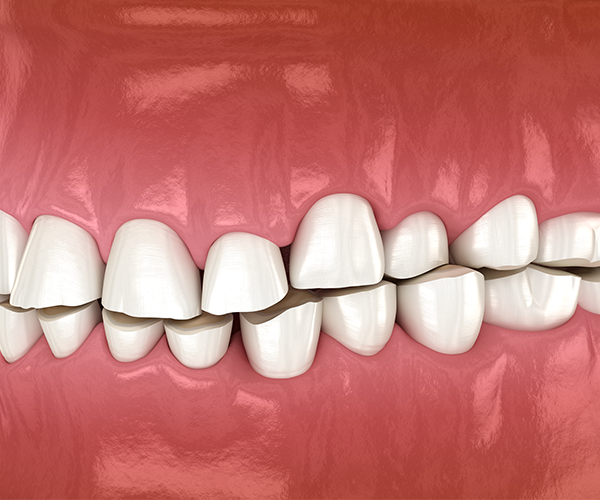

Check List

이갈이의 증상

• 1

치아 마모